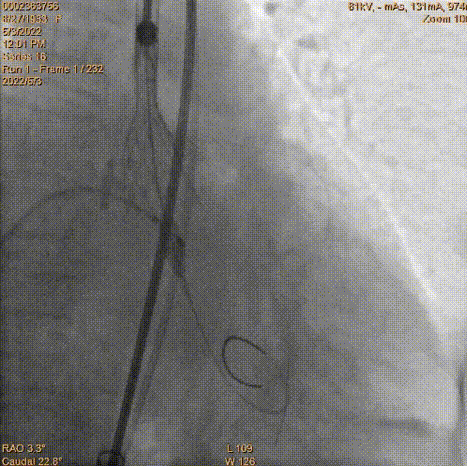

瓣膜定位

工作位造影

工作位冠脉球扩

瓣膜释放2/3同时发现患者血压降低,立即释放冠脉支架